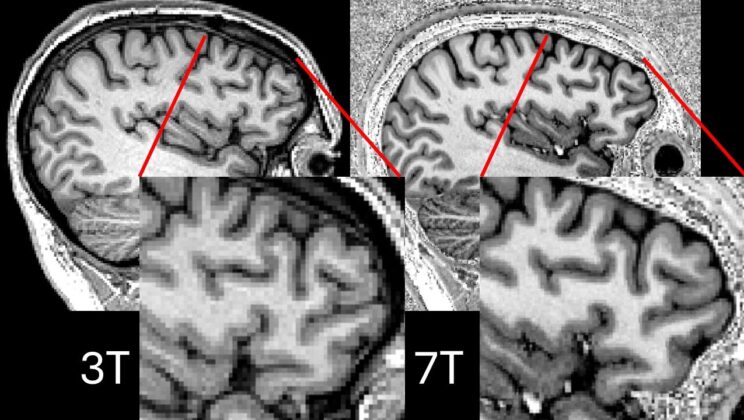

New 7T MRI Technique Reveals Hidden Epilepsy Lesions

For decades, patients with drug-resistant epilepsy have faced a harrowing uncertainty. When medications fail, and seizures persist, the only known…